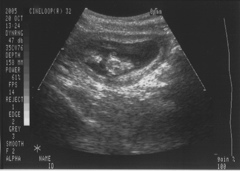

DSCF0029.JPG baby-print